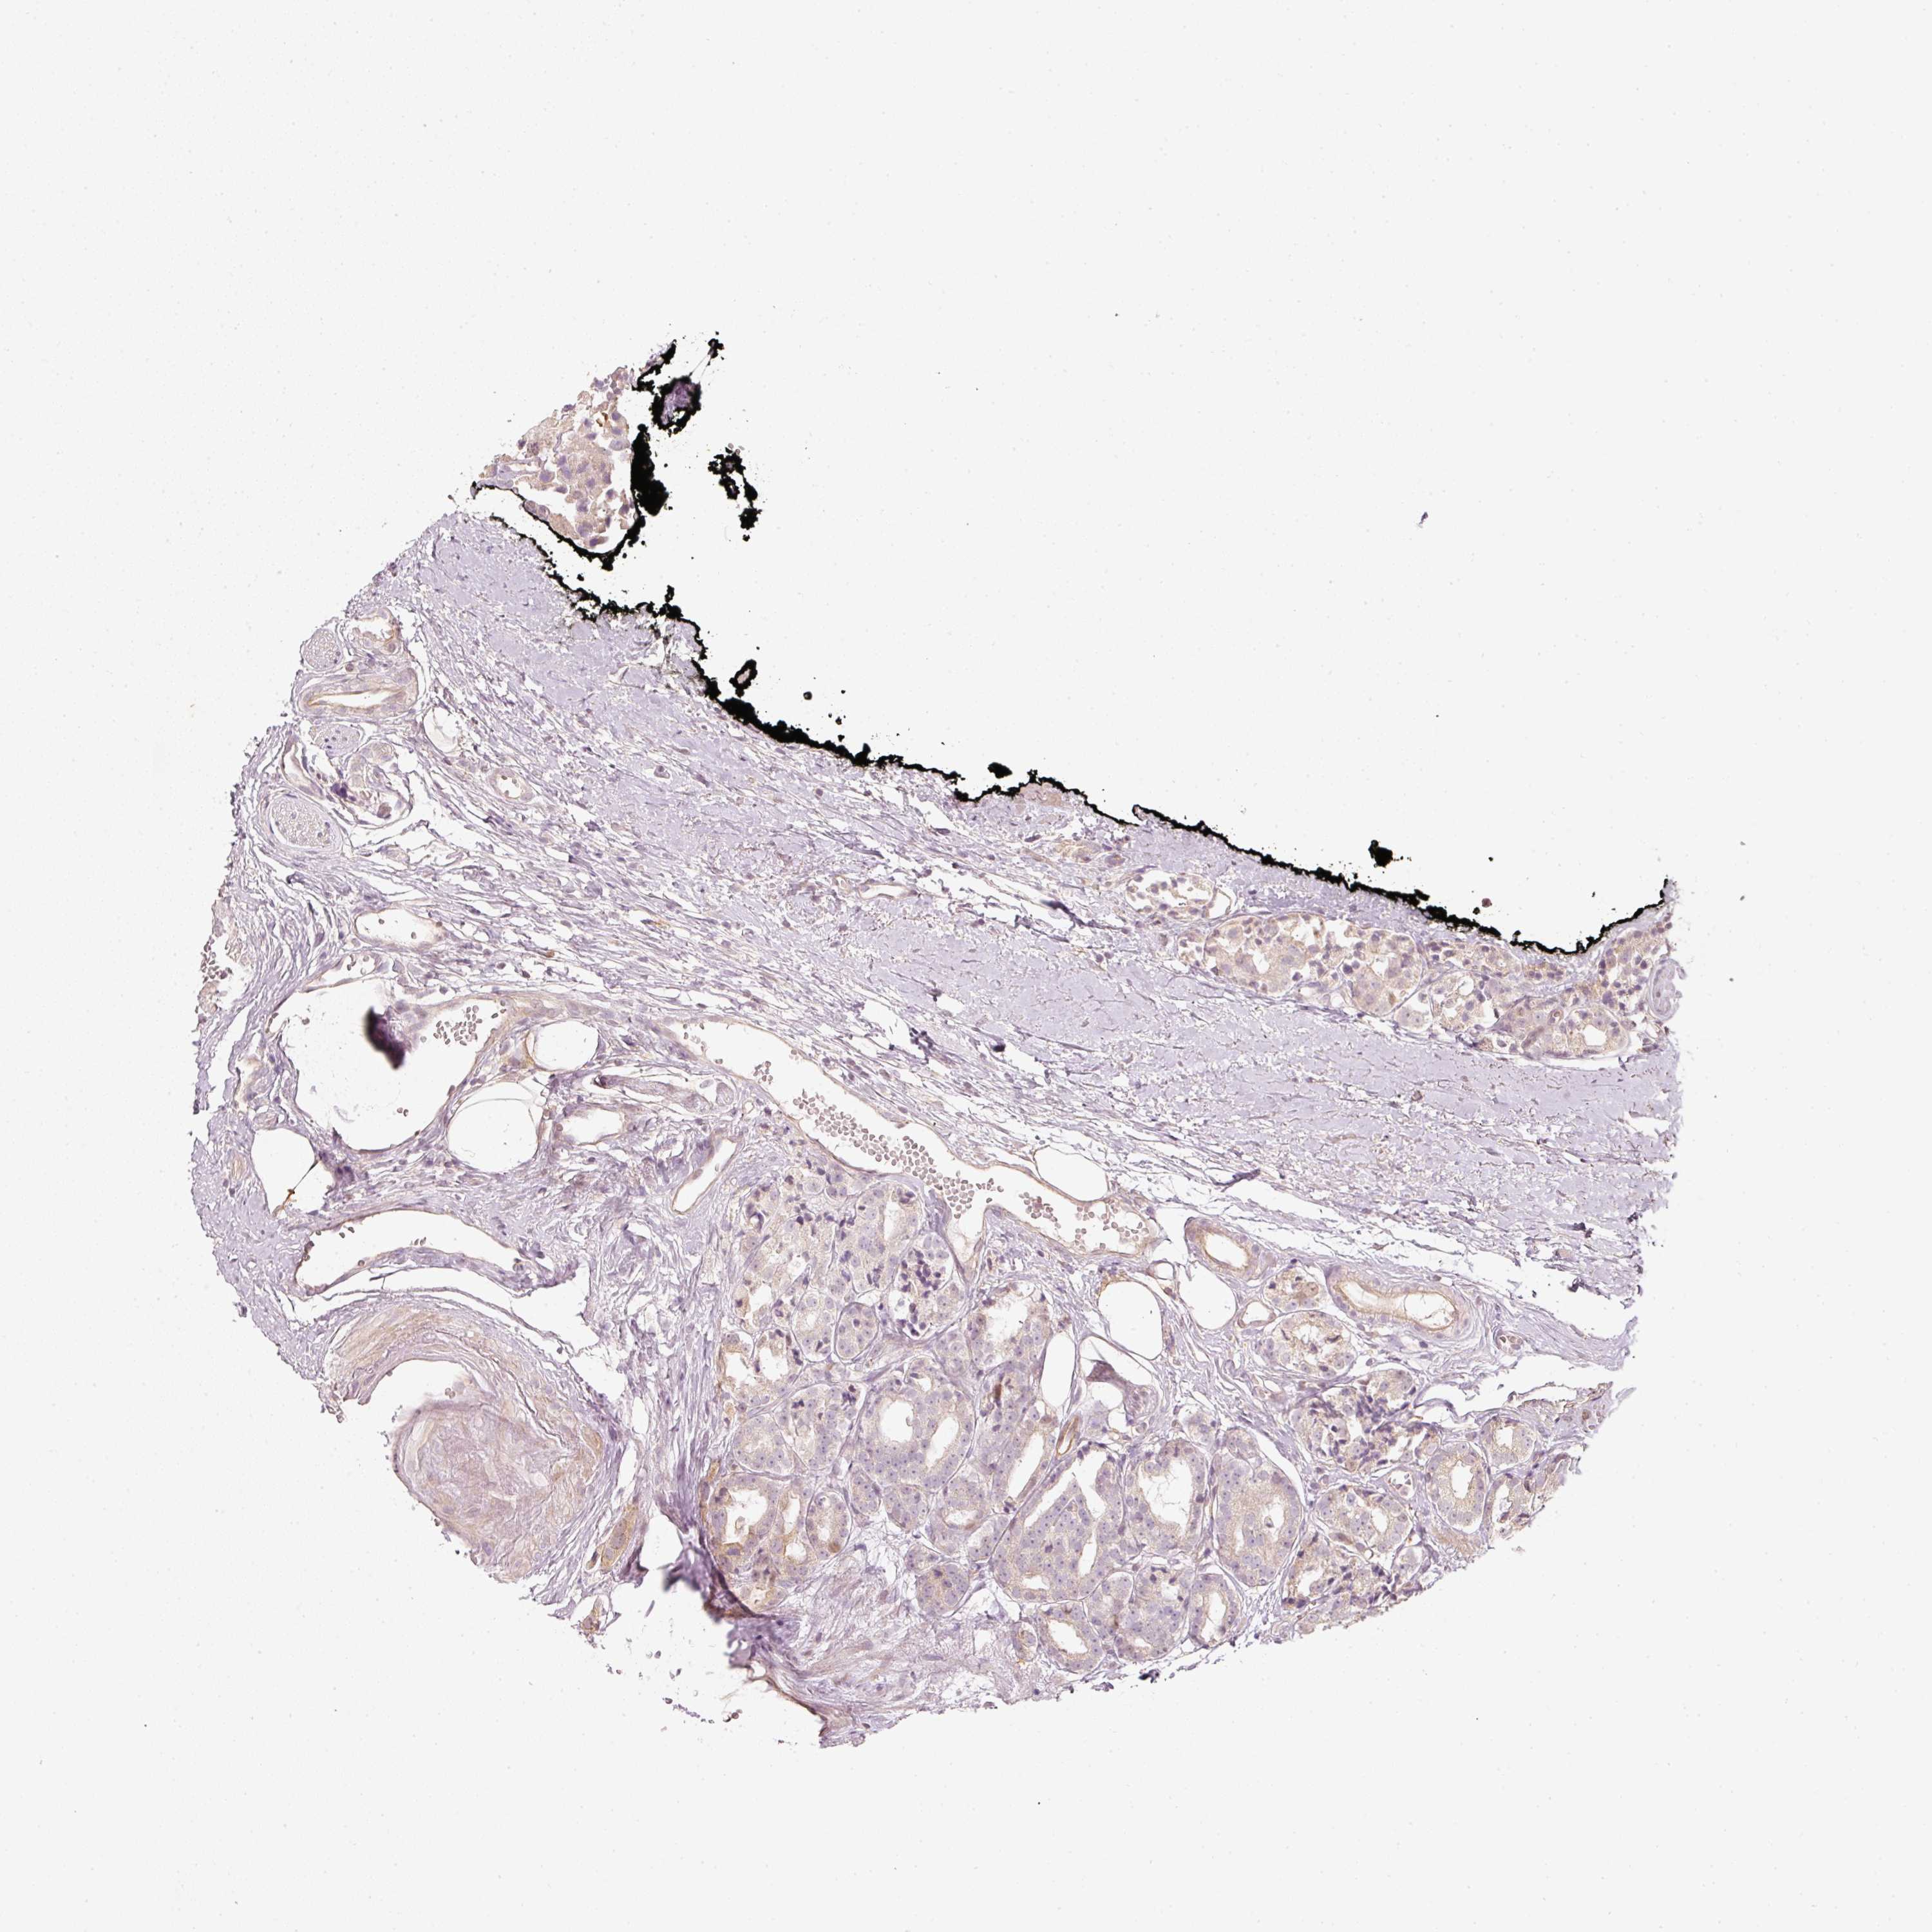

PROSTATE CANCER - Protein expressioni

A mouse-over function shows sample information and annotation data. Click on an image to view it in a full screen mode. Samples can be filtered based on level of antibody staining by selecting one or several of the following categories: high, medium, low and not detected. The assay and annotation is described here.

Note that samples used for immunohistochemistry by the Human Protein Atlas do not correspond to samples in the TCGA dataset.

Antibody stainingi

Antibody staining in the annotated cell types in the current human tissue is reported as not detected, low, medium, or high, based on conventional immunohistochemistry profiling in selected tissues. This score is based on the combination of the staining intensity and fraction of stained cells.

Each image is clickable and will lead to virtual microscopy that enables deeper exploration of all samples and also displays staining intensity scores, fraction scores and subcellular localization as well as patient and tissue information for each sample.

Antibody HPA054060

Staining

High

Medium

Low

Not detected

Intensity

Strong

Moderate

Weak

Negative

Quantity

>75%

75%-25%

<25%

None

Location

Nuclear

Cytoplasmic/membranous

Cytoplasmic/membranous,nuclear

Adenocarcinoma, High grade

Adenocarcinoma, Low grade